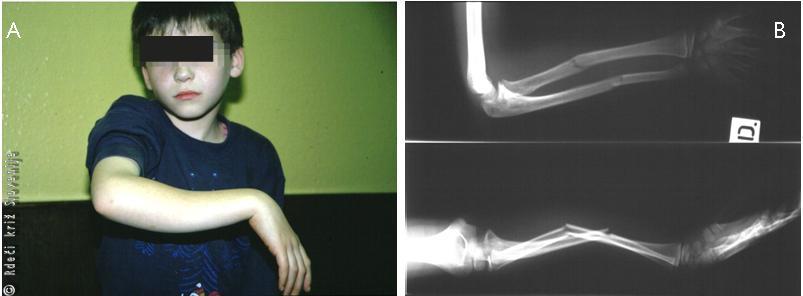

Slika 15

Zlom podlahtnice in koželjnice v srednji tretjini tipa »zelena veja« pri otroku.

A – Vidna je spremenjena oblika in oteklina.

B – Potrditev diagnoze z rentgensko sliko v dveh projekcijah.